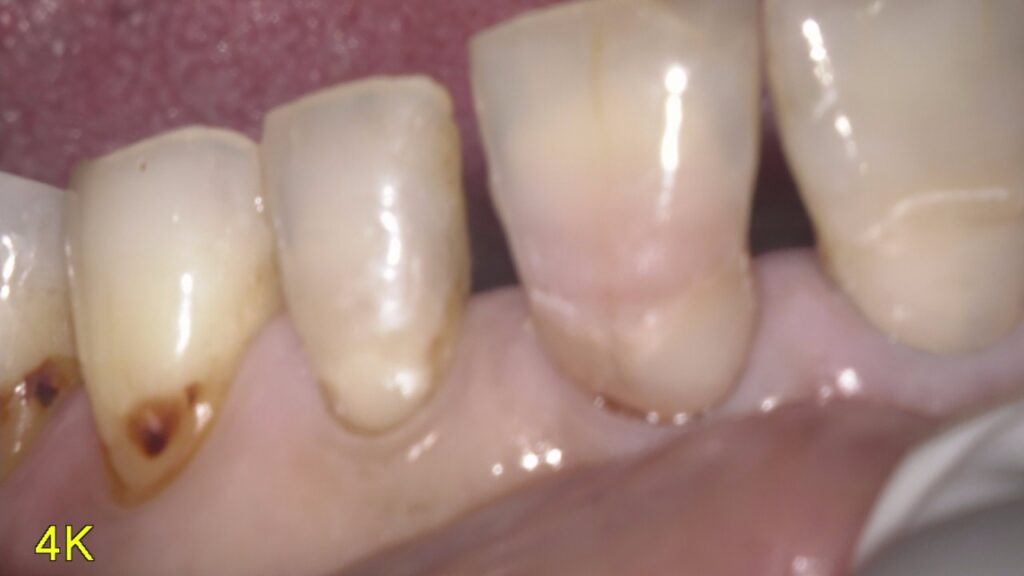

根面う蝕とは

加齢や歯周病により歯茎が下がると、丈夫なエナメル質に覆われていない歯根が露出していきます。この部分が虫歯になることを「根面う蝕」といいます。

根面はエナメル質に覆われていないので、虫歯はすぐに象牙質に達してしまいます。象牙質はエナメル質よりも軟らかく、酸にも弱く溶けやすいため、根面う蝕は通常の虫歯よりも進行が早いという特徴があります。

根面う蝕は「しみる」「ズキズキする」といった自覚症状がほとんどありません。歯の根元にできる虫歯のため唇で隠れやすく、虫歯のある場所によってはレントゲン撮影をしても発見が難しいため、気づいたときには虫歯がかなり進行していることもあります。

根面う蝕は歯と歯茎の境目に沿って横に進行していきます。そのため通常の食べ物をかむ部分にできた虫歯よりも削りにくく、詰め物をすることも難しいです。状態によっては根面う蝕を取り除くために、虫歯になっていない部分を削る場合もあります。さらに治療を受けた歯は脆くなりやすいです。